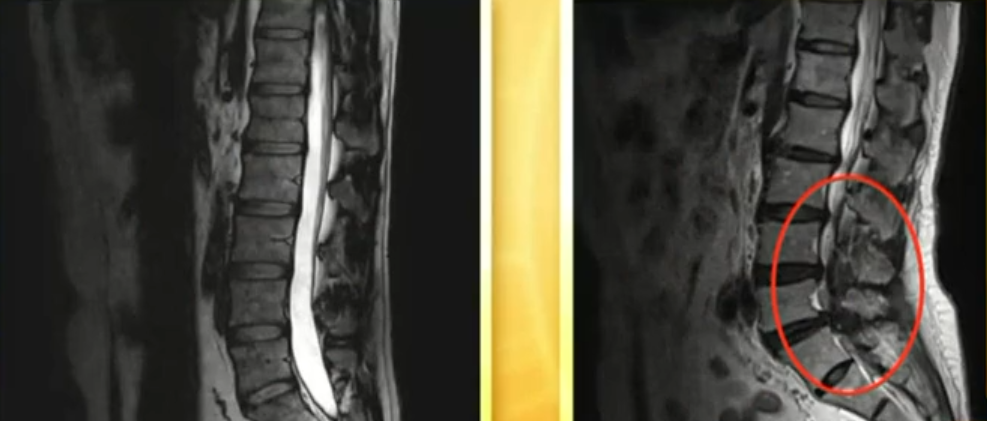

后来又上网买了5盒,贴完腰疼腿麻、坐骨神经痛全好了!不放心去医院查了下,腰椎间盘突出基本好了!我太感谢那个老中医了~